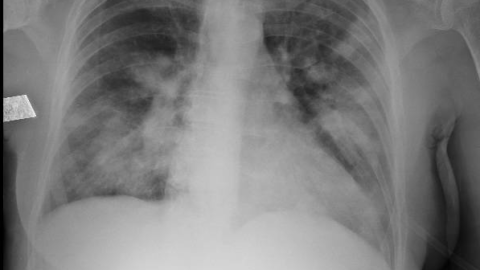

A los pocos meses se reinterna por encefalopatía en contexto de hiponatremia y sospecha de neumonía por infiltrados bibasales. Laboratorio con leucopenia, TSH 26 mUI/L, hipergammaglobulinemia policlonal de 2,9 g/dl. Recibe tratamiento con PTZ/oseltamivir con cultivos negativos. Evoluciona sin mejoría clínica. TC de encéfalo normal. PL con hiperproteinorraquia, resto de físico químico normal, cultivos negativos.

El siguiente evento es la internación con hiponatremia, encefalopatía e infiltrados bibasales. Sobre estos últimos, tenemos imágenes previas? Los infiltrados tenían apariencia intersticial? El SS está asociado a diferentes patrones de enfermedad pulmonar intersticial. Pudo ese haber sido el problema en los pulmones?

– Los infiltrados pulmonares impresionaban de sobrecarga hídrica en zonas de decúbito (no se incluyeron aquí por cuestiones de espacio).